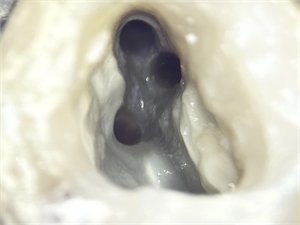

Root canal orifices of a molar tooth - clinical picture taken under microscope

Endodontics is the area of dentistry that cleans and fills the root canals. O the picture you can see the openings of the canals or so called root canal orifices

A root canal orifice is an important landmark in operative dentistry. Root canal treatments are usually done to eliminate all the infective material from the root canals of the tooth. In order to do so, the dentist needs to first deroof the pulp chamber. Once the pulp chamber is removed, the dentist can locate the root canal orifices.

In most cases, the root canal orifices are equidistant from each other. However, this is uncommon in upper back teeth. When the dentist drills the tooth to gain access to the root canal, then the cavity thus made must be enlarged enough for proper visualisation of the floor. The root canal orifices are present at the junction of the walls and the floor of this cavity.

The root canal orifice is the point where the dentist introduces his instruments in order to clean and shape the root canals. In many cases the root canal orifices are too small and it might be difficult to pass an instrument through it. In such cases, an orifice opener bur is used to widen the orifice. The procedure to locate the root canal orifices is similar in deciduous or milk teeth as well. The only difference is that the orifices are located at a relatively higher position due to the decreased length of the tissues and hence are found earlier. On a digital radiograph, a close inspection of the pulpal floor might reveal a few blackish spots, that often correspond to the root canal orifices. This is particularly useful in cases where orifices are not located at the conventional areas.